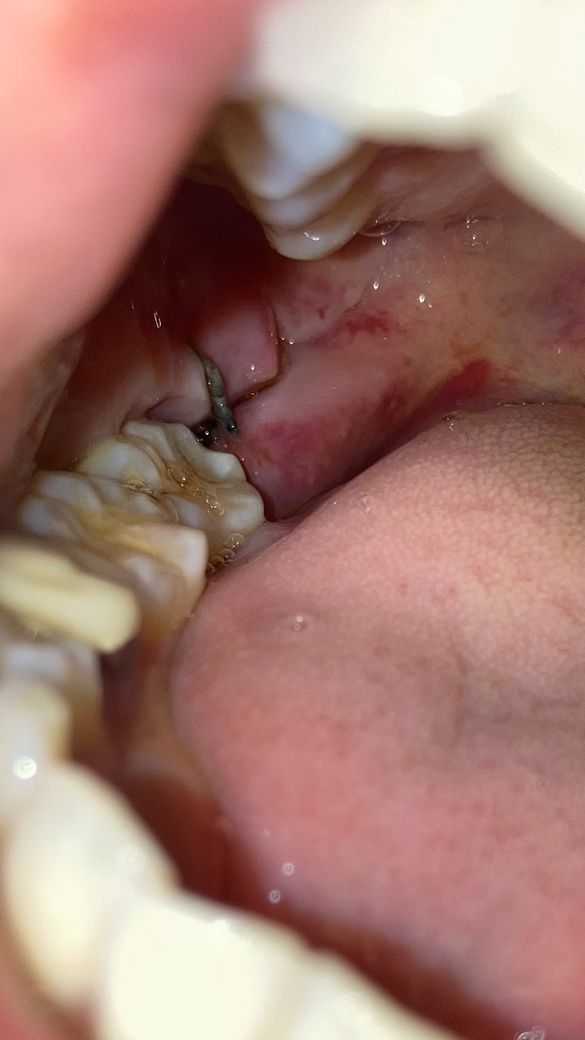

사랑니 치료가 잘 된건가요 ..절개가 너무 많이 되어보이네요 ㅠ

사랑니 발치하고 이제 5일차 인데 핸드폰을 찍어서 보니까 잇몸 절개가 위쪽까지 길게 되어 있더라구요 ..

치료는 잘된건지 회복은 잘되고 있는건지 사진상으로 봤을때는 어떤가요 ??

사진상으로 염증이 있어 보이거나 하지않기에 잘 아물어 가고 있는 것으로 보입니다. 해당부위 염증이 덧나지 않도록 소독용 헥사메딘 가글액으로 가글하여 관리하여 주길 권합니다.

잇몸절개는 부분,전체매복 사랑니 발치 시 일반적으로 행해지는 진료입니다. 사진상 치유가 지연되거나 그래보이진 않습니다. 해당 부위 위생관리 잘해주시기 바랍니다.

사진 상 염증 등의 문제는 보이지 않습니다. 절개된 부위 등은 시간이 지나면서 잘 붙게 됩니다.

사랑니를 발치할때는 사랑니가 위치되어 있는 상태에 따라서 절개정도가 달라지게 됩니다.

잇몸은 절개가 되어 있어도 잘 아물기 때문에 크게 문제가 되지 않습니다.

사진상으로는 크게 문제가 잇어 보이진 않습니다. 최대한 음식물이 끼지 않도록만 관리를 해주세요.